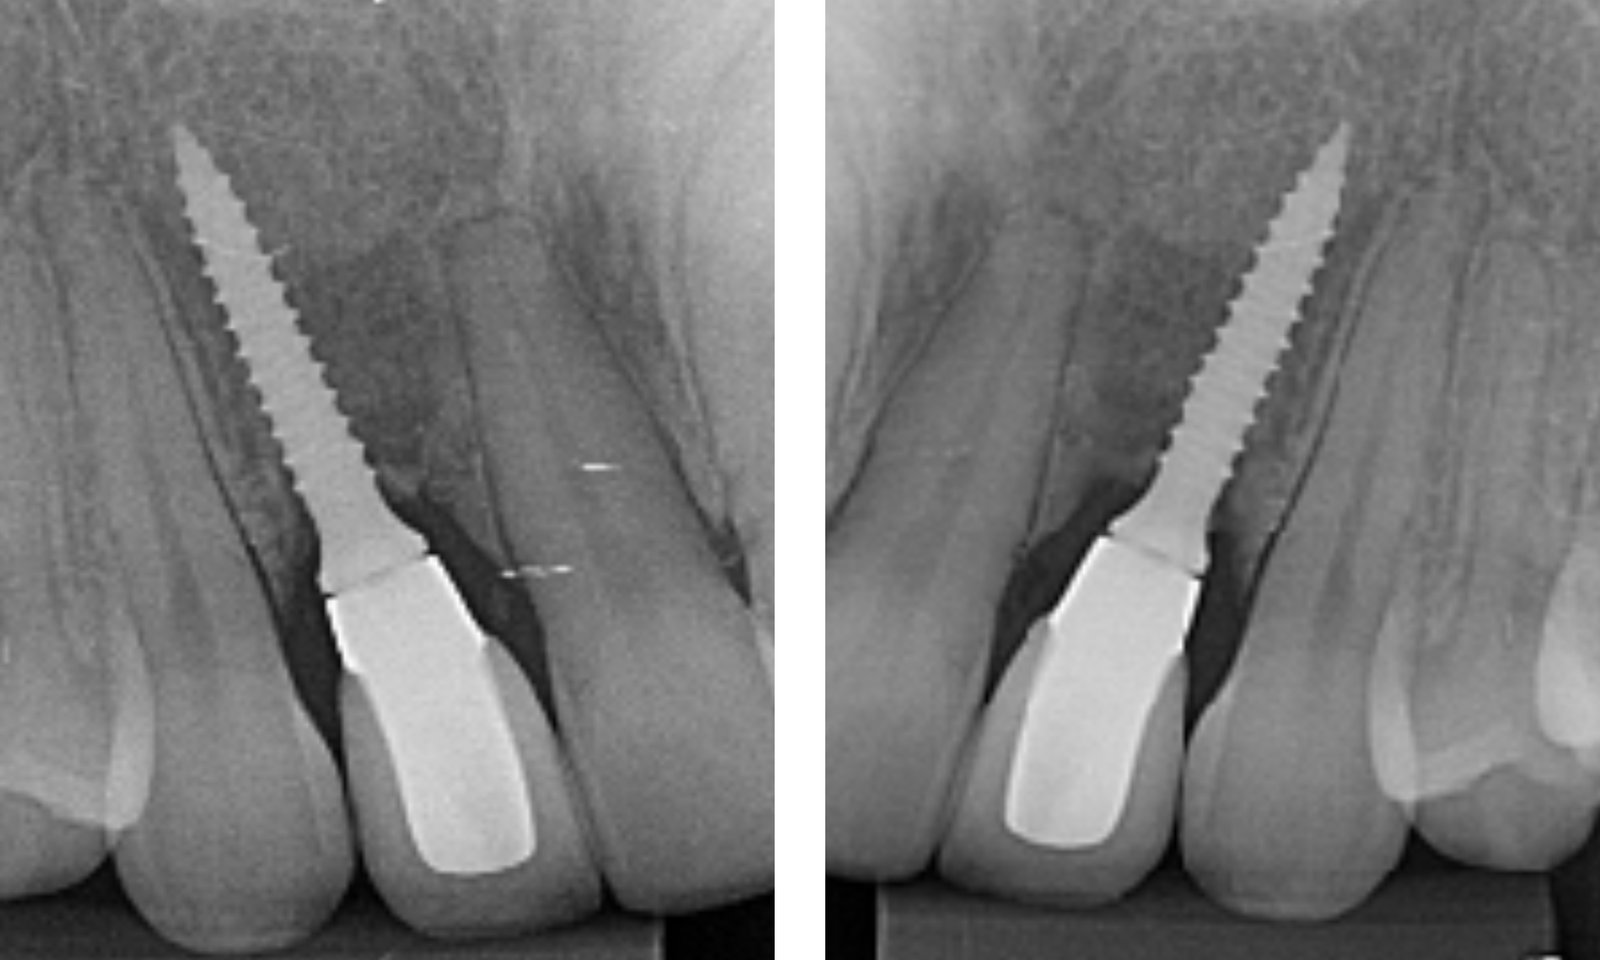

foi realizado a exposição do leito regenerado,

instalação de implantes Implacil Slim 2.5 x 13mm, associado a enxerto de tecido conjuntivo para aumento dos tecidos moles na zona de transição no sulco perimplantar.

Após temporização por 3 meses, foram restauradas as incisais dos caninos bilateralmente, para devolver as guias de lateralidade , e finalização protética das coroas sobre os implantes.